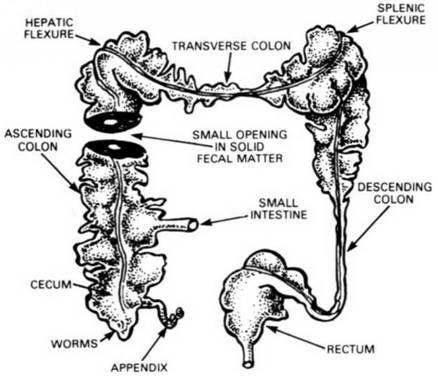

BELOW: What happens when the COLON FAILS TO RECEIVE NECESSARY COLON IRRIGATIONS.

THIS ILLUSTRATES THE LOWER PART OF THE ASCENDING COLON, SHOWING THE APPENDIX AND THE ILEOCEAL VALVE WITHIN THE JUNCTION OF THE SMALL INTESTINE WITH THE ASCENDING COLON.

The ileo - cecal valve is equipped with a safety mechanism which opens automatically to let matter pass through from the small intestine into the colon, but closes automatically to prevent any substance, liquid or solid from returning into or entering into the small intestine from the colon. If this happens, YOU'RE IN TROUBLE.

The ileo - cecal valve opens into the colon in a pouch known as the cecum which is somewhat larger than the other pouches constituting the colon. It is the first receptacle for waste residue.

The cecum does not always empty its contents into the colon immediately, and from this point onward we must, patiently and with tolerance, study this subject in some detail, whether we like it or not, as this region is one of the most vital areas controlling our indisposition, malady and infirmity on the one hand, or VIBRANT HEALTH on the other hand.

The prolonged retention of fecal matter in the colon may accumulate to such an extent that the walls of the colon may become thickly coated with such matter as you will see dramatically portrayed in the accompanying illustration. In this picture you will notice the colon has been cut across a section of it to show the thick impacted wall of the colon which has left only a tiny opening through the center for waste matter to pass through.

The walls of the colon have an important function to perform, namely the squeezing of its contents to extract as much as possible of the liquid nourishment remaining in it, and pass this liquid by osmosis through the walls of the colon for diffusion throughout the body. A thickly impacted wall makes this function impossible of performance. The victim of such an impacted colon, may, under such conditions even have several "bowel movements daily without discomfort, but this condition is neither normal nor indicative of health! In fact it is an extremely dangerous situation as a complete blockage of the colon could take place at any time.

When a complete blockage of the colon has occurred, the surgeons usual practice, in order to save the victim's life, is to perform a colostomy, the formation of an artificial anus by an opening into the colon from the outside of the skin. For the rest of the victim's life his feces evacuations take place through a tube into a bag hanging from his waist. Isn't it better to prevent this horrible procedure? Personally, 1 would prefer to die, rather than to subject myself to such an affliction.

BADLY IMPACTED COLON: